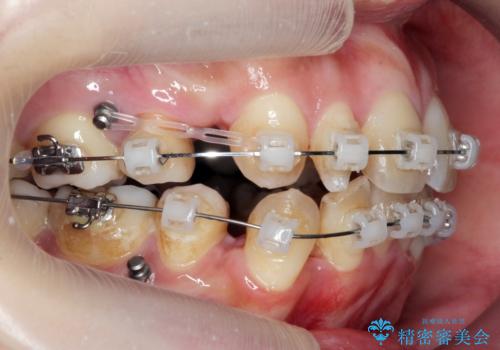

重度のがたつき 矯正治療+セラミック治療で綺麗な歯並びに 矯正専門では難しい治療

- 歯並びを気にして来院。

乳歯が残存しており、また左上の犬歯もずれて生えてきていました。

右上の前歯も細長い特殊な形をしていました。(矮小歯といいます)

矯正治療で歯並びを治した後、乳歯を抜いたところにブリッジを入れています。

左上の奥歯はすれ違っていたためそのかみ合わせも整えています。